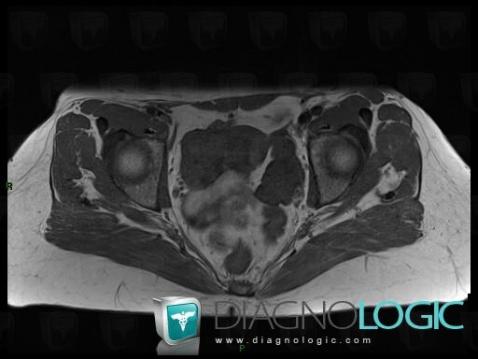

The images below illustrate this case for diagnoses Fibrothecoma, for the modalities (MRI)

Fibrothecoma, Adnexa / Ovary fallopian tube, Pelvis / Perineum, MRI

- Diagnosis Fibrothecoma, Location(s) Adnexa / Ovary fallopian tube, with gamuts Solid adnexal massPelvis / Perineum, with gamuts Solid pelvic mass